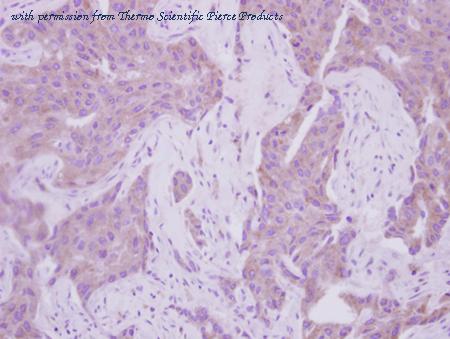

- Cdk5rap1 antibody